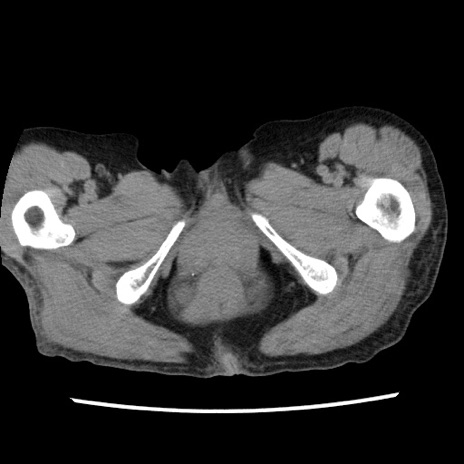

症例1(横断像)

【症例】80歳代女性

【主訴】腹痛

【現病歴】8時間前から腹痛あり来院。

【既往歴】糖尿病、脂質異常症、子宮体癌にて子宮全摘術

【身体所見】意識清明・会話良好だが腹痛で苦悶様、全腹部にわたって反跳痛と圧痛あり

【データ】WBC 13600、CRP 0.14、LDH 224、CK 90